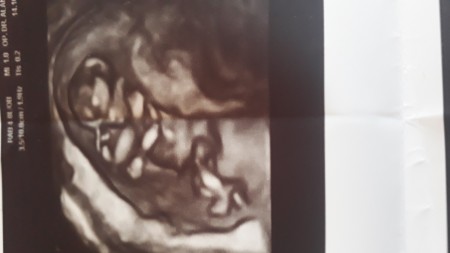

imageiki kızım var bu bebegimin cinsiyetini merak ediyrum

Gebelik haftası 12 haftalık

Bana erkek gibi geldi

Yapısı erkeğe benziyor sanki. Erkek bebeklerde bu kadar belirgin olur derler uzuvları. İnşallah gönlünden geçen olur sağlıkla.

Vala sağ taraf erkek sol taraf kız derler bana göre sola yerleşmiş kız olabilir ama masaalh büyük erkekte olabilir ikinci hamileliğim erkek ikisinde ve sağ yerleşim yaptı sonuç erkek;)